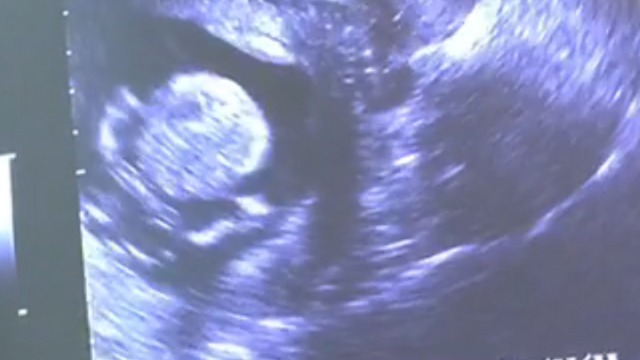

18週3日(18w3d・女の子)|よーちゃん、! さん(27歳)

エコー写真撮影時のエピソード:

妊娠7ヶ月のプレママです。

妊娠6ヶ月に入るまで、私は胎動を全く感じませんでした。

このエコー写真の時期はもちろん胎動がなく、赤ちゃんが無事に生きているのかとても心配でした。

そんな時エコー写真で赤ちゃんの背骨をはっきり見ることができて、大きくなってきているのだなあととても嬉しくなりました。

赤ちゃんってだんだんと人間らしくなっていくのですね。

パパにエコー写真を見せた時、これが背骨だよっと教えると、すごいなあーとびっくりしていました。

産まれるまであと3ヶ月です。

赤ちゃんに会えるのが楽しみです。